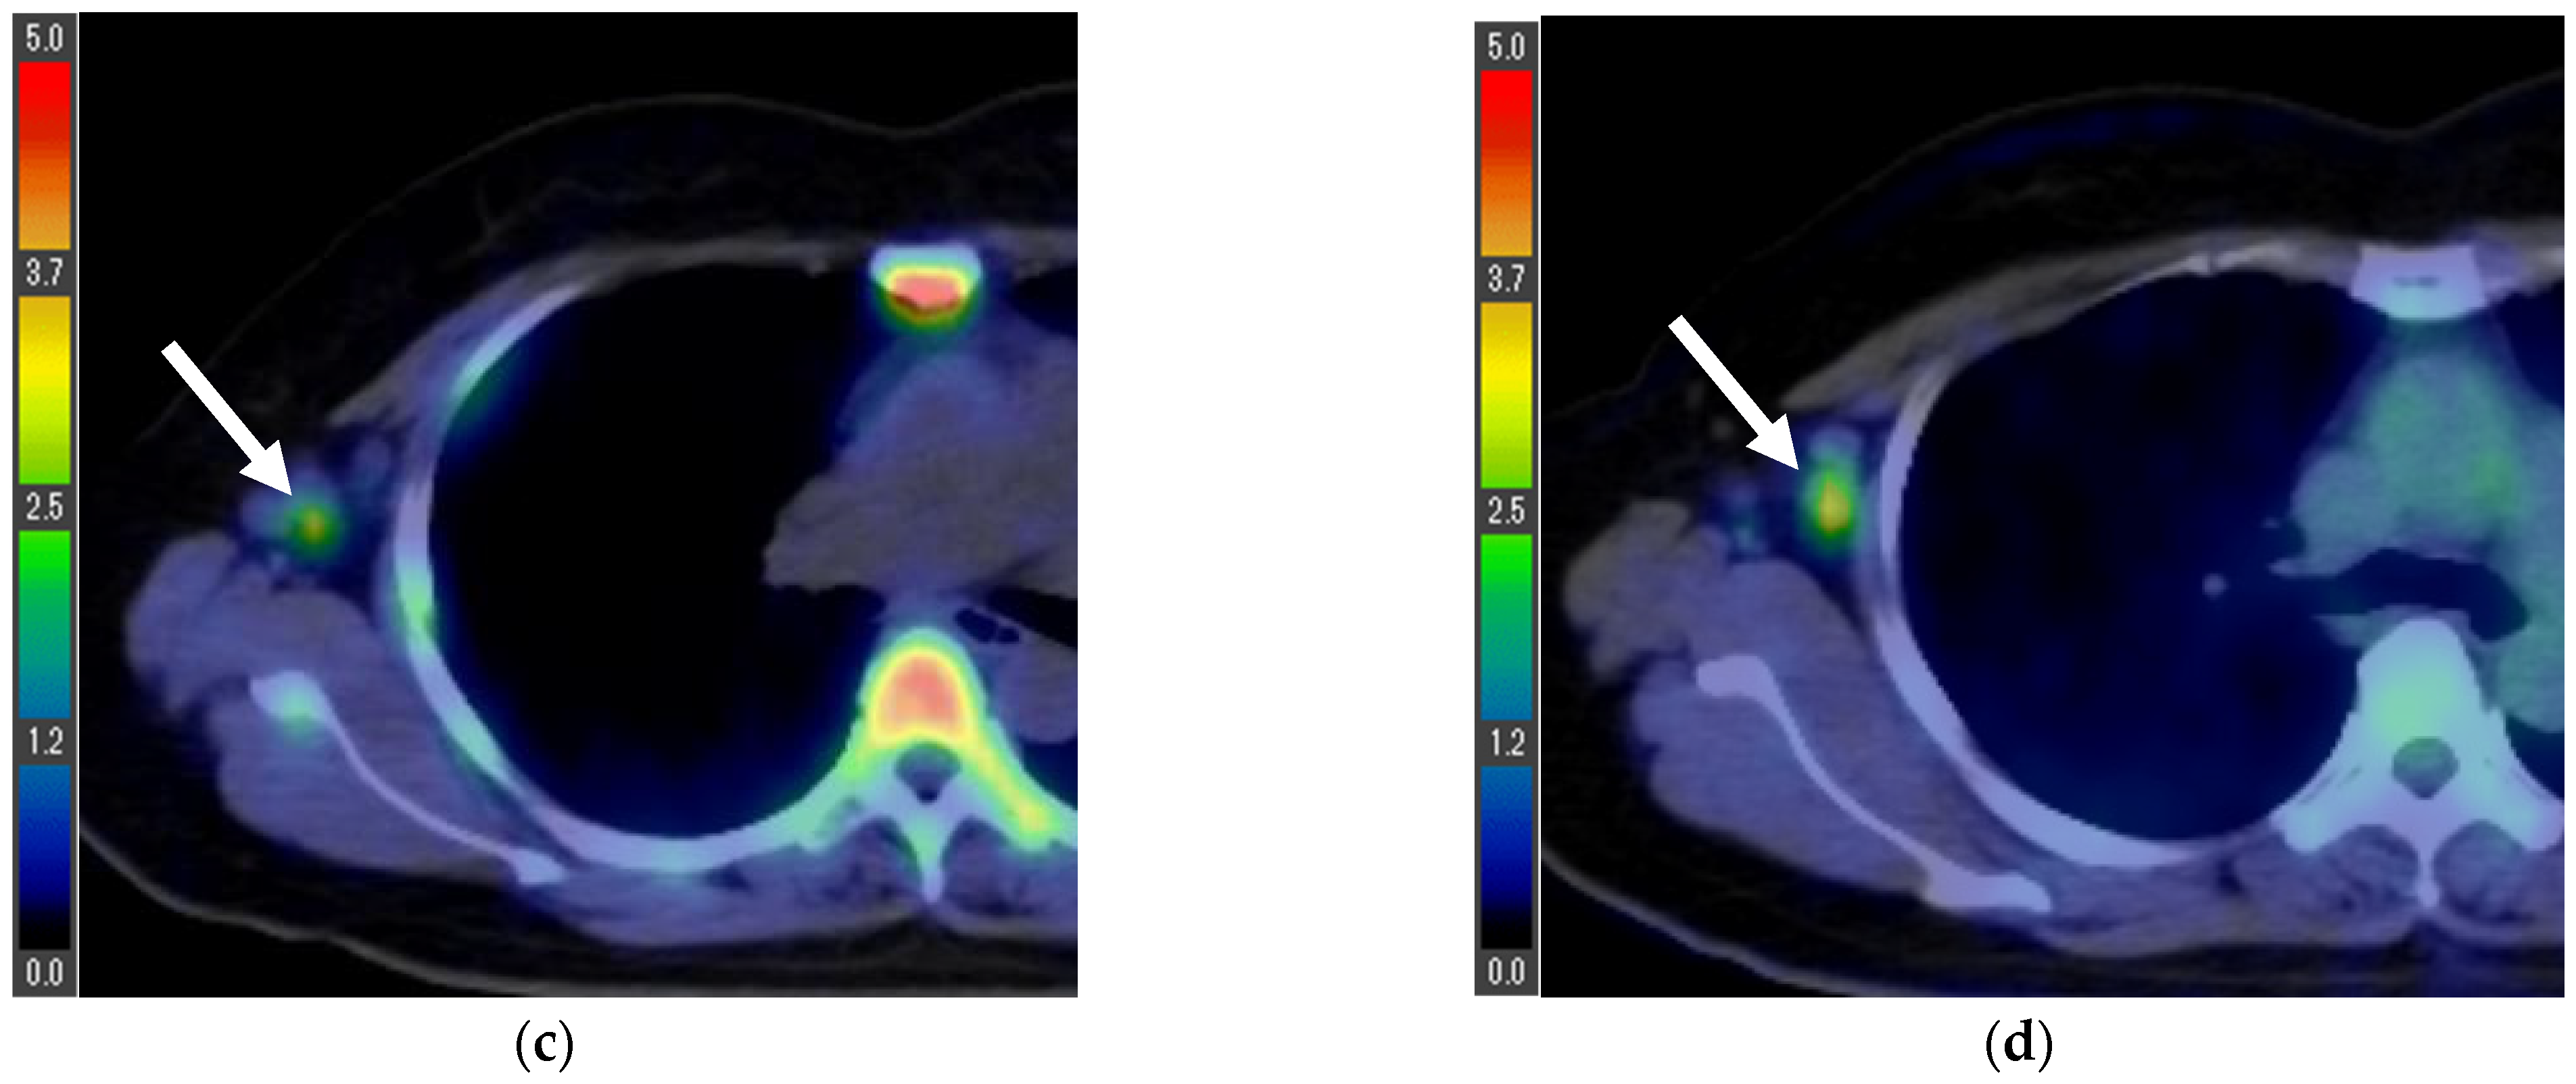

| 1 | 1.0 | 1.8 | 1.6 * | 3.4 * | T1cN2aM0 ** | Invasive ductal carcinoma | 1 | + | + | − | 1.0 |

| 4 | 0.4 | 1.5 | 16.7 * | 14.2 * | T1bN3aM1 *** (Lymph node and bone metastases) | Invasive ductal carcinoma | Data loss | + | + | − | Data loss |

| 5 | 3.8 | 8.3 | 1.8 | 6.3 | T2N3bM0 *** | Invasive ductal carcinoma | 1 | + | + | − | 25 |

| 6 | 4.8 | 8.4 | 1.4 | 3.2 | T4bN1M1 *** (Lumbar vertebra metastasis) | Invasive ductal carcinoma | 1 | + | + | − | 8.9 |

| 7 **** | 7.0 | 10.1 | 1.2 | 0.7 | T4bN0M0 | Invasive ductal carcinoma | Data loss | − | − | + | 59 |

| 8 ***** | - | - | 1.1 | 4.1 | N3bM1 (Lymph node, lung, and bone metastases) | Invasive ductal carcinoma | 3 | + | − | + | 29.3 |